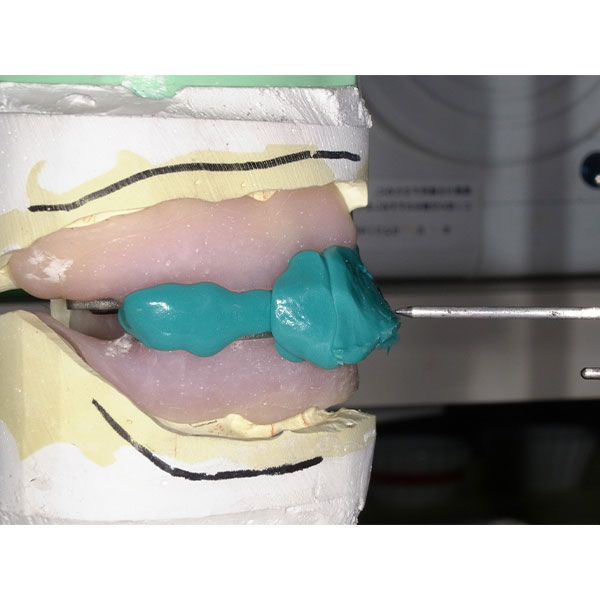

Après la mise en moufle et l'ébouillantage, les dents ont été repositionnées, conditionnées et des caractérisations blanchâtres, pourpres, orange clair, bleues et roses ont d'abord été réalisées au niveau du le bouclier labial. La base a ensuite été incrustée de résines pour prothèses de couleurs orange-rouge, rouge foncé, rouge clair, rose et rose foncé, et tous les polymères à chaud ont été pressés en une seule fois. Après le stockage sous pression, les prothèses finies ont été démouflées, finies et polies. La stratification anatomique tridimensionnelle de VITAPAN EXCELL en masse d'émail, de collet et de dentine avait un aspect absolument naturel dans l'anatomie muco-gingivale reproduite de la base prothétique. Le patient a pu s'habituer rapidement à sa nouvelle prothèse, notamment grâce à l'effet esthétique réussi. Après une courte phase d'adaptation et des corrections minimes dans l'environnement biodynamique, il s'est très bien débrouillé avec sa première restauration prothétique amovible complète et en était pleinement satisfait.